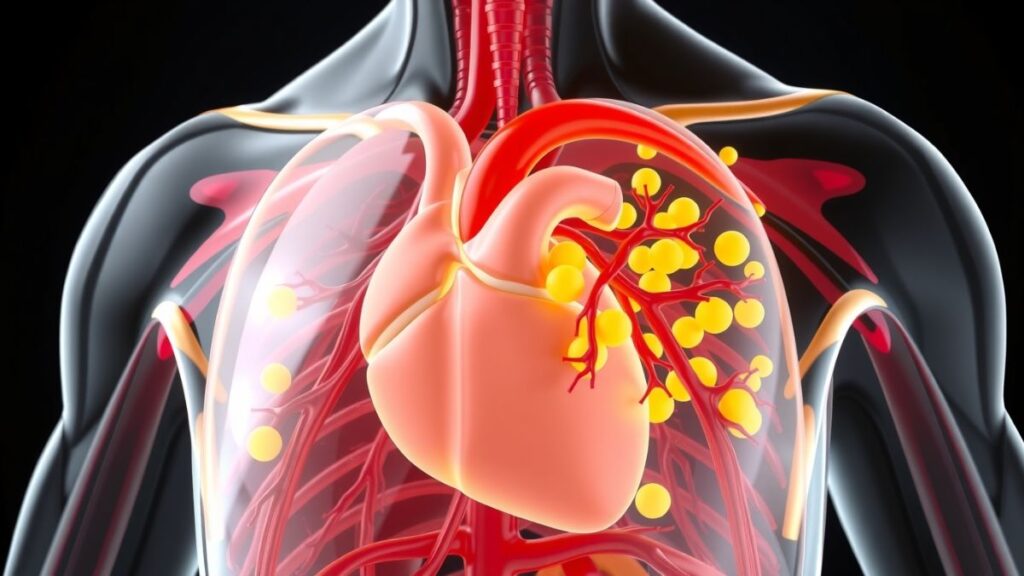

बढ़े हुए कोलेस्ट्रॉल का हमारे शरीर पर क्या प्रभाव होता है?

उच्च कोलेस्ट्रॉल सिर्फ दिल ही नहीं, पूरे शरीर को प्रभावित करता है। इसके कारण

- पैरों में दर्द और सुन्नपन

- जल्दी थकान

- आंखों के पास पीले धब्बे

- हाई ब्लड प्रेशर

जैसी समस्याएं शुरू हो जाती हैं। लेकिन इनमें सबसे खतरनाक होता है कोलेस्ट्रॉल का हार्ट पर प्रभाव, क्योंकि दिल की बीमारी कई बार बिना चेतावनी के हमला कर देती है।